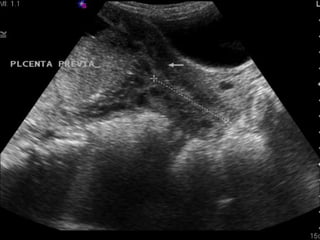

Placenta Previa

Placenta implants too low

Painless bright red bleeding

Risks: prior C-section, grand

multiparity, previous previa,

multiple gestations,

multiple induced abortions,

mom >40.

Management: U/S, Ob consult,

pre-op labs,

pre-op labs, avoid pelvic

avoid pelvic

exam,

exam, c-section

c-section